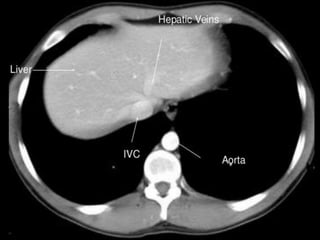

CT cross sectional

anatomy.